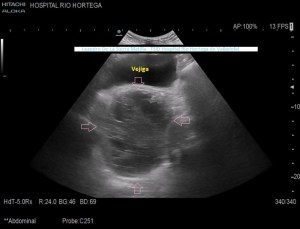

Se realiza estudio de Ecografía Abdominal protocolizado, en el que se observan entre otros hallazgos, varias lesiones esplénicas y ováricas (flechas rosas) junto con una mínima cantidad de líquido libre abdominal.(FIG 1,2 y 3)

1

2

3